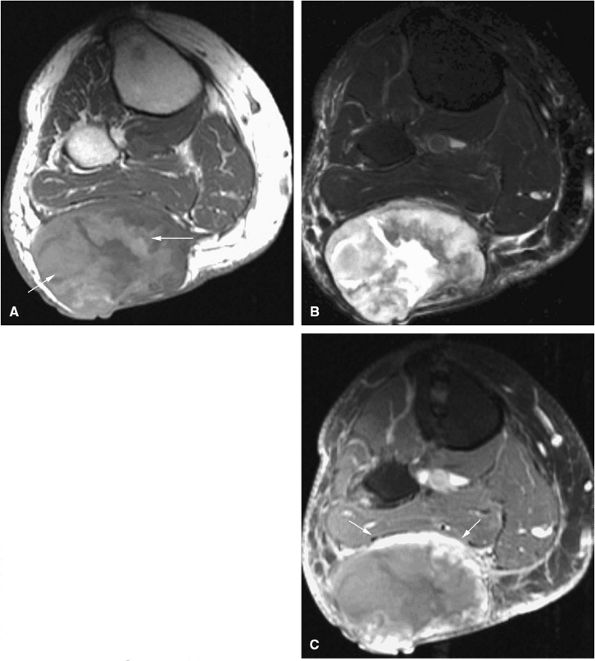

FIGURE 14-52 ● Aneurysmal bone cyst of the talus is eccentric and expansile (arrows), as seen on sagittal T1-weighted image (A). Fluid–fluid levels (arrows) are seen on sagittal (B) and axial (C) fat-suppressed T2-weighted fast spin-echo images and an axial proton density-weighted image (D). Septal enhancement (arrows) is noted on this fat-suppressed T1-weighted axial image (E) following administration of intravenous gadolinium.

The expansile lesion may have internal septations, fluid–fluid levels, and areas of bright signal intensity on both T1- and T2-weighted images, depending on the chronicity of the associated hemorrhage (Figs. 14-52 and 14-53).77

The fluid–fluid level probably represents layering of uncoagulated blood within the lesion.78 On T1-weighted images, increased signal intensity in the gravity-dependent layer represents methemoglobin. It may be difficult to exclude the possibility of malignancy when severe inhomogeneity of signal intensity is observed.

Cortical bowing and septation (trabeculation) may be seen in a low-signal-intensity contour of cortical bone.